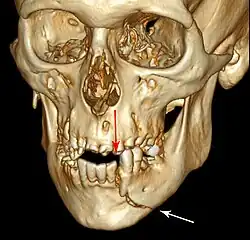

3D computed tomographic image of a mandible fracture in two places. One is a displaced right angle fracture and the other is a left parasymphyseal fracture.

Computed tomography is the most sensitive and specific of the imaging techniques. The facial bones can be visualized as slices through the skeletal in either the axial, coronal or sagittal planes. Images can be reconstructed into a 3-dimensional view, to give a better sense of the displacement of various fragments. 3D reconstruction, however, can mask smaller fractures owing to volume averaging, scatter artifact and surrounding structures simply blocking the view of underlying areas.